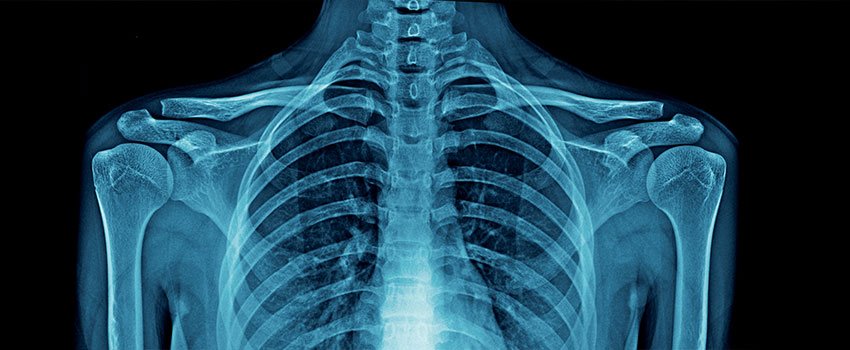

Our platform provides access to a rich and diverse collection of medical datasets designed to support research, innovation, and advanced analytics in healthcare. These datasets span multiple clinical domains and imaging modalities, enabling comprehensive analysis and model development.